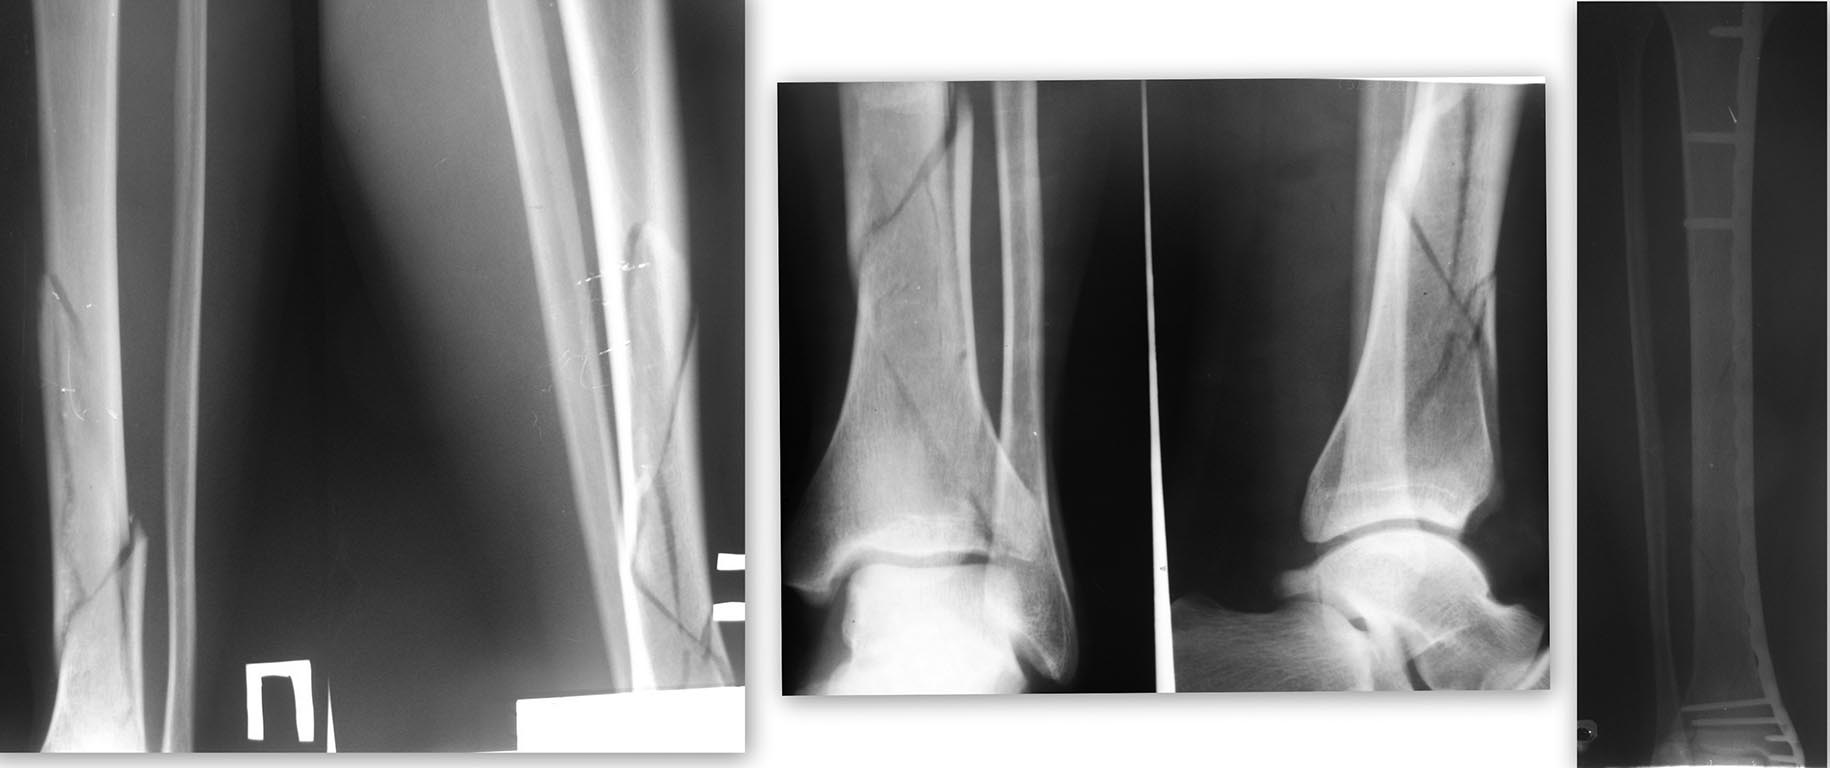

Доброго времени суток! Может как-то так? Закрытая репозиция, мостовидная фиксация. Случаю 4 года, функциональный результат хороший(прошу прощения за качество снимков)